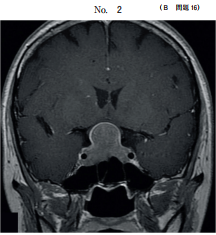

44 64 歳の男性。呼吸困難を主訴に来院した。日前に左胸痛と息切れとが出現し、 次第に増悪してきたため受診した。体温 36.2 ℃。脈拍 100/分、整。血圧 120/80 mmHg。呼吸数 20/分。SpO2 92 %room air 。眼瞼結膜と眼球結膜とに異常を認 めない。頸部リンパ節を触知しない。左胸部に呼吸音を聴取しない。血液所見赤 血球 420 万、Hb 13.0 g/dl、Ht 37 %、白血球 4,400桿状核好中球%、分葉核好 中球 60 %、好酸球%、好塩基球%、単球%、リンパ球 25 % 、血小板 21 万。 CRP 0.4 mg/dl。来院時の胸部エックス線写真別冊No. 4 を別に示す。入院後、 胸腔ドレーンを挿入したところ、直後から咳嗽と泡沫状の喀痰とが出現した。この 時点の胸部エックス線写真別冊No. 4 を別に示す。 胸腔ドレーン挿入後の病態として正しいのはどれか。